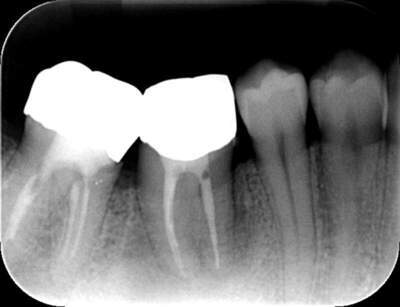

2021.4.3 定期検診時

この時はまだ症状がなかった

しかし歯は縦に割れており、いつ痛みが出てもおかしくないような状態であることは説明していた。

2022.1.15 根尖性歯周炎の急性化

疼痛ありで急患来院。

前々から爆弾抱えているような物で、何かあったら抜歯と伝えていた部位。以前よりクラウンマージン下で歯根縦破折であったが、症状なしで経過観察をおこなっていた。